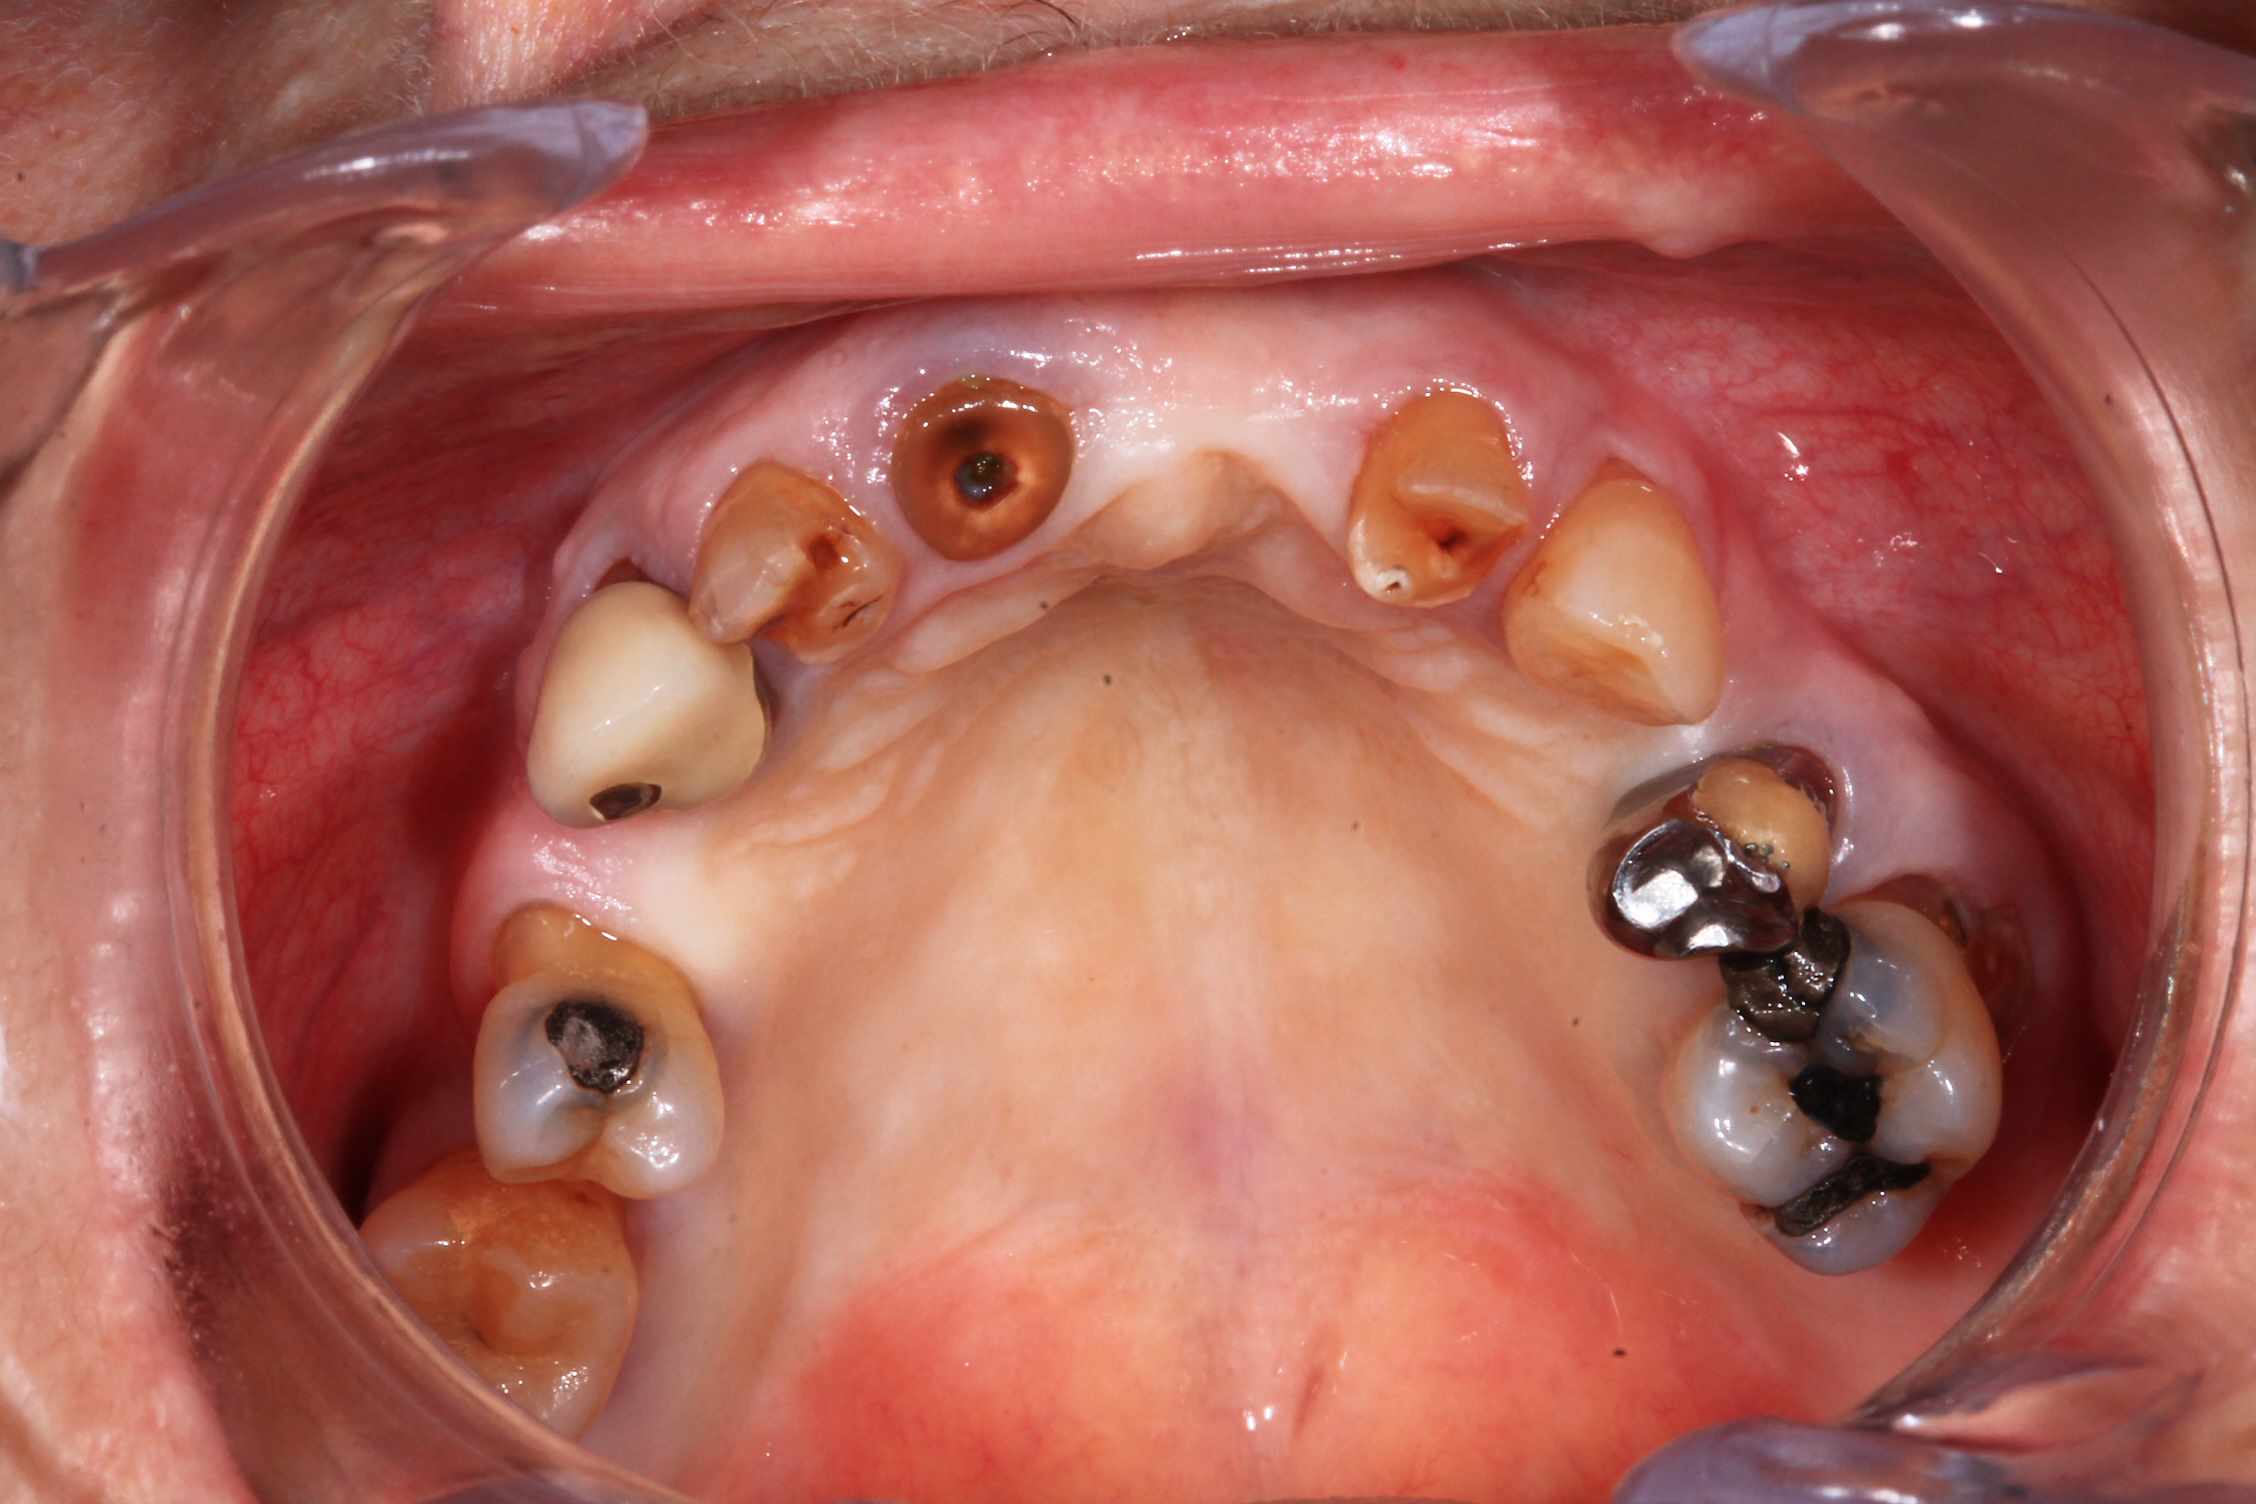

Cas 5 : extraction et all on 4. en bas , pas du tout d'os : décision de bridge complet avec une extension de chaque coté.

Modélisation : labo lio. Design et impression du guide : Teeth projet. Bridge full zircone katana myio rosenscrew en mise en charge instantanée , labo LIO.

Guide a etage avec fixtion de l'etage clavette par rapport aux dents avant extraction. Extraction.